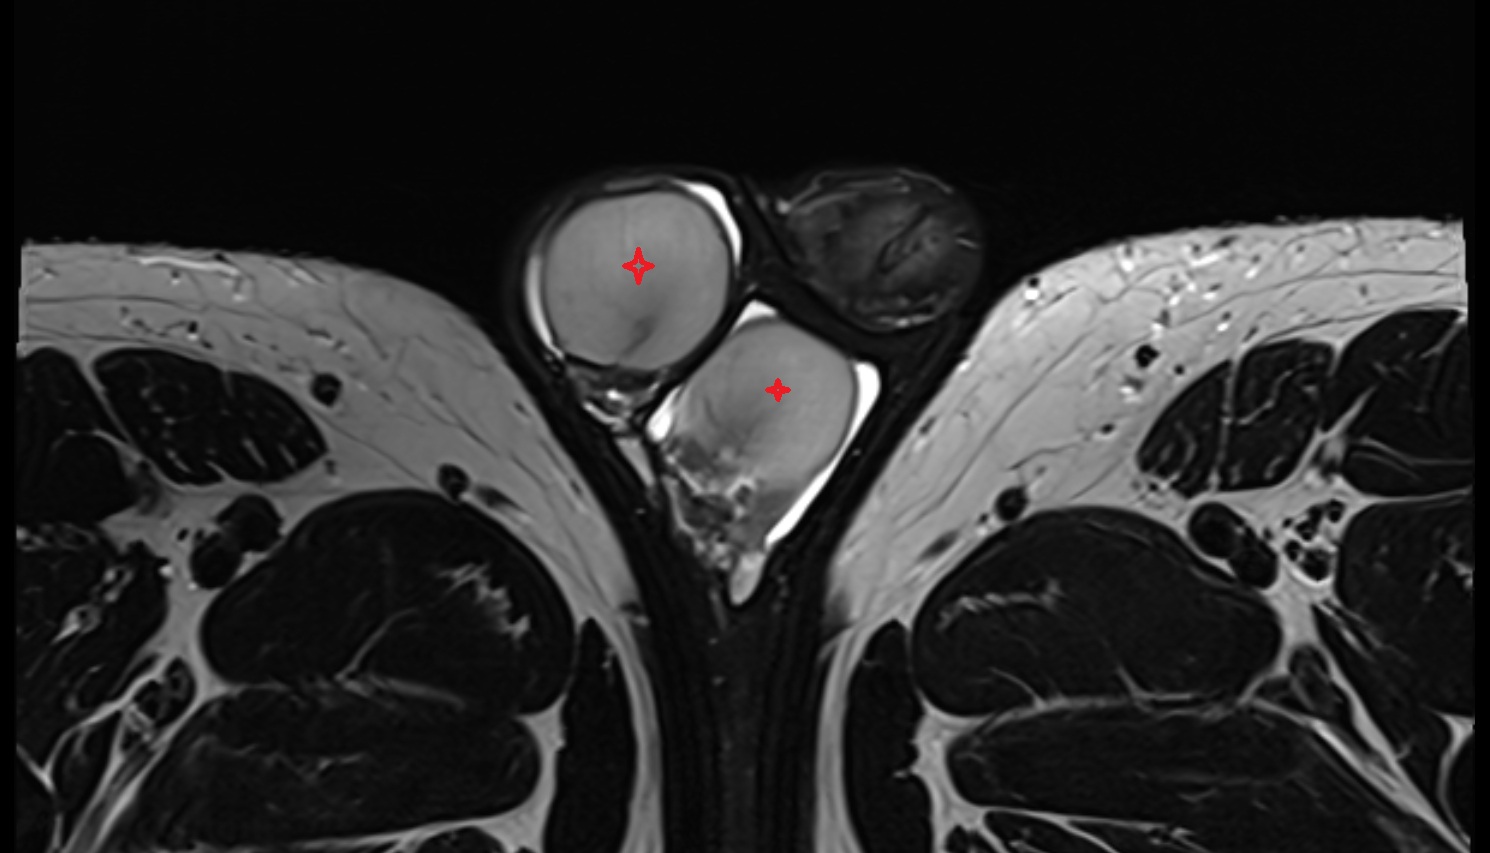

- Corpus cavernosum

- Corpus spongiosum

- Bulb of Penis

- Crus of penis

- Testis

- Tunica albuginea (penis)

- Tunica albuginea of testis

- Septum of scrotum

- Skin of scrotum

- External spermatic fascia

- Cremaster fascia

- Internal spermatic fascia

- Parietal tunica vaginalis

- Lobule of testis

- Mediastinum testis

- Visceral tunica vaginalis

- Scrotal fluid

- Septum of testis